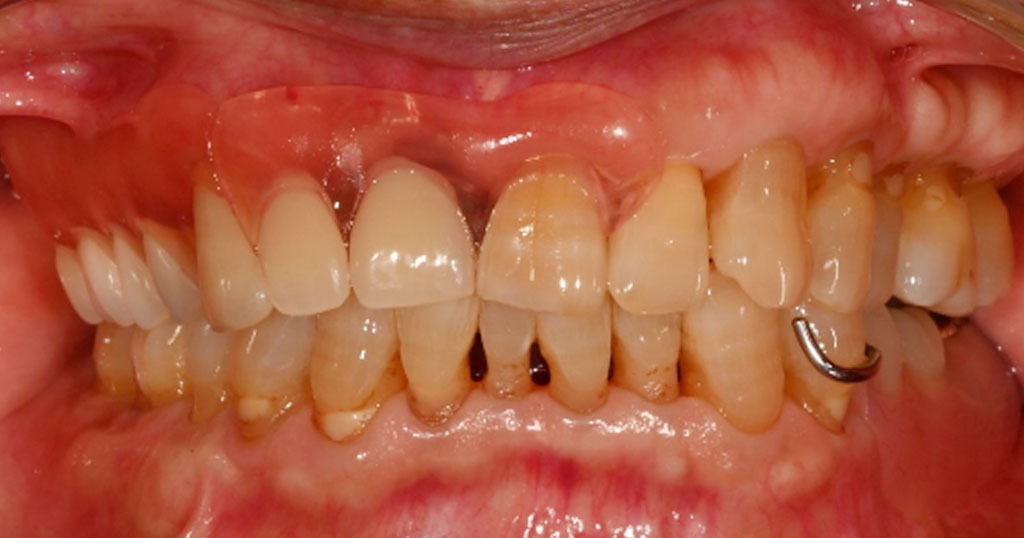

Before1

80代男性。上顎右124567番が欠損した状態で来院。今まで使用していた保険の入れ歯を使用しているが不満で、インプラント手術も怖いということで自費の入れ歯をご希望とのこと。